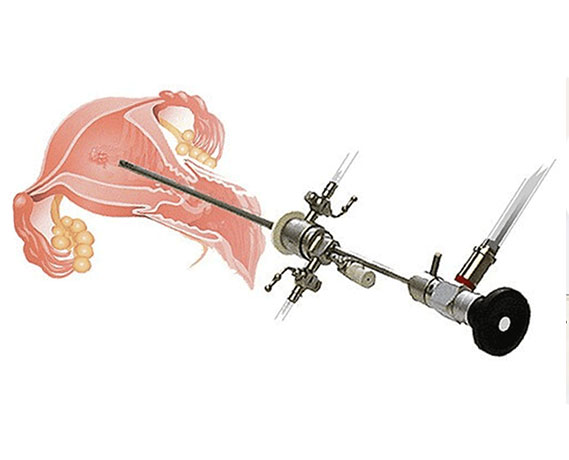

- Histeroskopik Ameliyatlar

- Miyom Ameliyatı